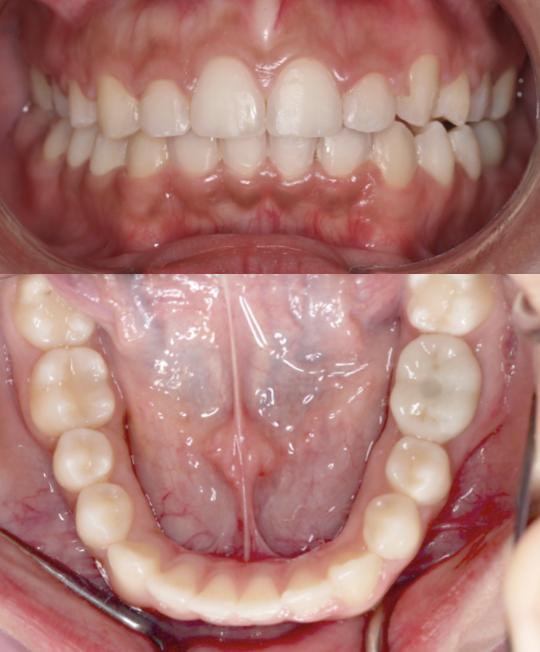

Full Mouth Rehabilitation

A severe bruxism case restored with a combination of two strategically placed dental implants and full monolithic zirconia crowns to rebuild strength, function, and aesthetics. This comprehensive rehabilitation was successfully completed at Moral Dental Clinic, delivering a stable bite, improved smile harmony, and long-term durability.